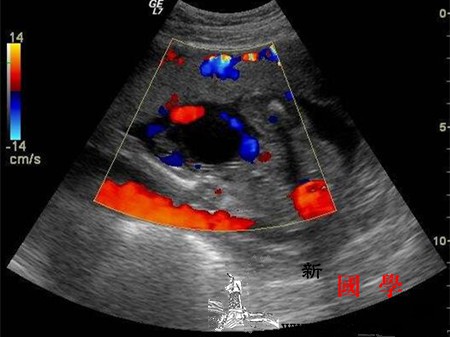

孕妇单脐动脉严重吗_泌尿系-染色体-超声-胎儿-

孕妇为什么会单脐动脉_染色体-血栓-胚胎-妊娠-

单脐动脉的宝宝出生后有问题吗_染色体-孕期-胎儿-动脉-